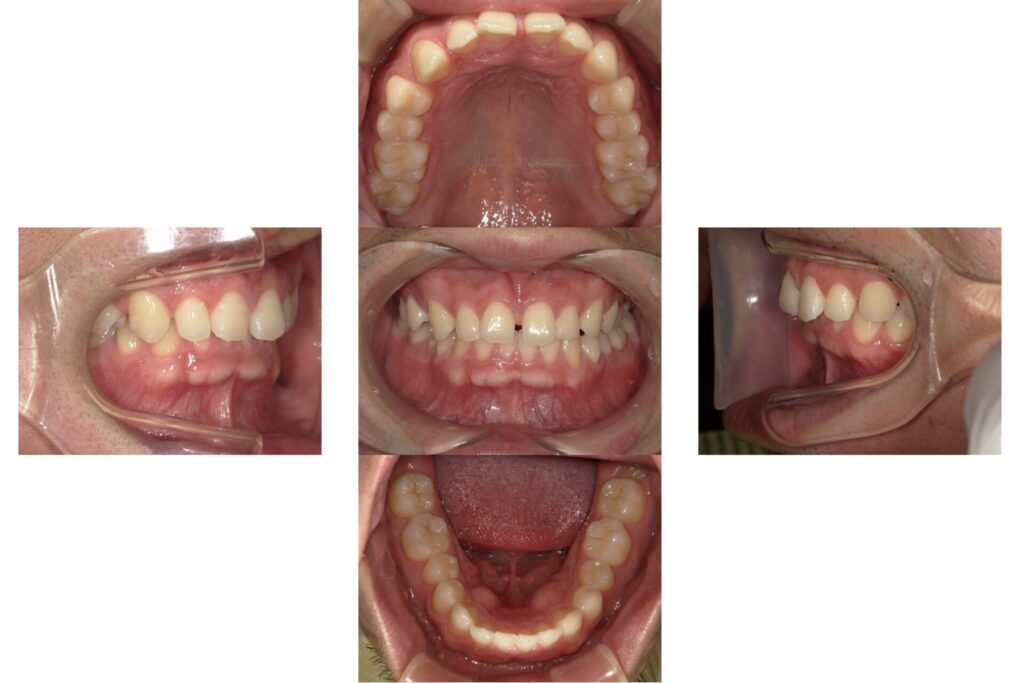

Before

| 備考 | 前歯の歯並びをきれいにしたいということで来院されました。 インビザラインGoにより、ガタガタしていた歯並びを整え、 審美性、機能性の改善を行っています。 |